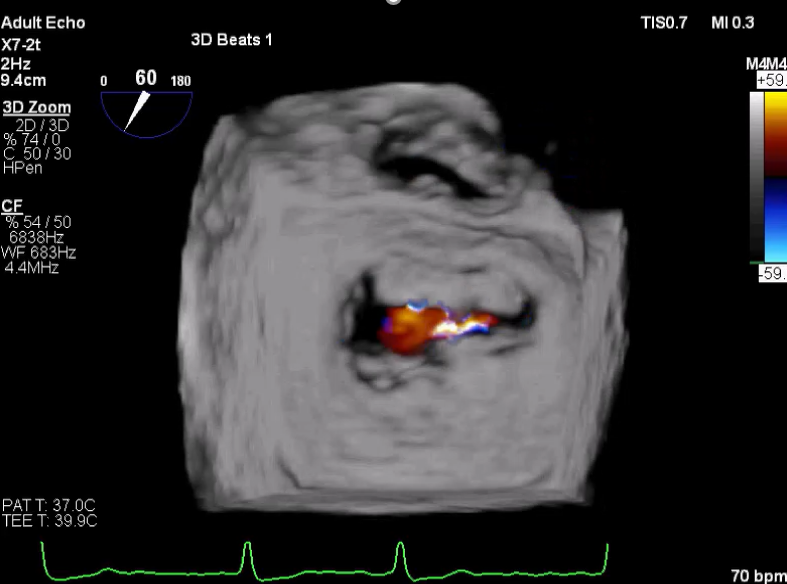

术前超声诊断

LVOT-color:MR(重度),返流面积11.3cm2

肺静脉血流频谱呈收缩期反向

3D-color MV view:血流主要来源于2、3区

Qlab软件勾画估测瓣口面积约:6.16cm2

TEE LVOT切面返流量评估

TEE 4-Ch view返流量评估

3D-color:残余少量返流